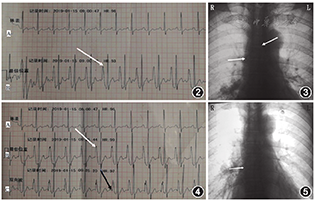

患者返回血管通道中心,重新对穿刺部位导管和皮肤进行消毒,根据胸部X线片上电子标尺测量导管打折长度约2.5 cm,故将导管从静脉中拔出3 cm,然后重新送入导管。连接科曼C100心电定位仪,4个电极片分别贴于右锁骨下(RA)、左锁骨下(LA)、左下(LL)腹部、右下(RL)腹部,屏幕抓取二导联心电波形原始资料记录患者基础心电图,取下RA导联,将无菌导联线鳄鱼夹一端夹在20 ml注射器注射针头针柄上,一端连接心电定位仪,采用生理盐水引导腔内心电图定位方法,心电图显示P波高尖,P波振幅等于QRS波振幅的1/2(图2),提示导管尖端位于SVC中、下三分之一。随后拍摄的CXR显示导管尖端位于SVC中段,导管末端仍然反折成L型(图3)。故进行第二次导管尖端位置调整,在心电图定位下,拔出部分导管,直到高P波消失。然后轻柔缓慢将导管再次送入血管至导管0刻度位置,观察P波振幅从正常到高尖,但未观察到负向P波改变,继续将导管0刻度后1 cm长度导管送入血管,观察到高尖P波前有一个负向小P波,即双向P波(图4)。最后,将导管拔出1 cm,导管外露0刻度。再次拍摄的CXR显示导管尖端位于SVC的下三分之一处(图5)。

文献报道PICC置管术中在没有任何实时尖端定位方法的情况下,原发性异位发生率高达32%[5],原发性异位类型多样,包括导管置管侧锁骨下打折、异位对侧锁骨下或颈内静脉等[6,7]。本案例导管末段部分打折,尖端在SVC内异位,较为少见。总结分析造成此类型异位原因为:(1)经左侧植入的PICC相对于右侧具有较高的异位率;(2)导管送入血管的速度过快导致其末段在上腔静脉内打折;(3)置管术中仅选择血管超声检查颈内静脉和锁骨下静脉,初步排除导管尖端异位,未正确采用实时尖端定位技术。在发现本例患者导管尖端异位后,我们将导管从血管中拔出3 cm,随后将其轻柔缓慢送入静脉,送管过程无阻力。采用ECG定位导管尖端,观察到高峰P波。然而,CXR显示导管尖端位于上腔静脉内,导管末端仍然反折成L型。总结导管尖端异位纠正失败原因如下:(1)后退导管距离仅为3 cm,不足以调整导管方向;(2)操作者受思维定势的影响,在P波波形评判上考虑不全面,主观认为腔内心电图显示明显的高P波变化,导管尖端位于上腔静脉内,不存在异位的风险,而未考虑到这一现象存在的可能,即使存在导管在上腔静脉内打折异位,只要导管尖端在上腔静脉靠近窦房结区域内,仍然可以引出明显的高尖P波变化;(3)操作者在ECG定位PICC尖端位置的操作中,有失规范,在完成送管操作后使用ECG定位导管尖端位置,仅观察到一个高的P波变化,没有观察典型完整的P波改变:从标准到高峰然后到双相的P波变化,高尖P波前有一个小的负向波表示导管尖端在右心房入口处[8]。在第二次调整导管尖端位置时,我们观察到完整的P波,从标准到高峰,然后到双相。最后,CXR显示导管尖端位于上腔静脉下段。